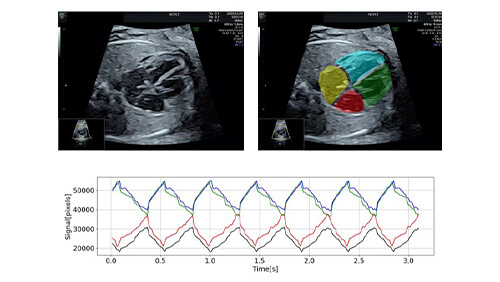

超音波診断動画による

胎児不整脈診断支援システム

- ・AIを用いて超音波動画のみで診断を支援するシステムを開発

- ・頻脈、徐脈、期外収縮などの不整脈を自動判別して診断支援する

システムのプロトタイプを完成